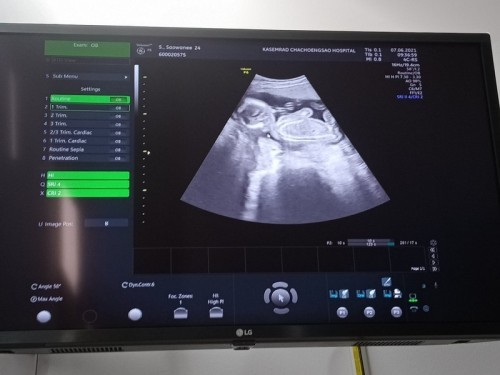

ภาพนี้ถ่ายตอนน้องอายุ22สัปดาห์❤️

คุณหมอบอกว่าได้ลูกผู้ชายคะ ร่างกายสมบูรณ์ดีคะ👶